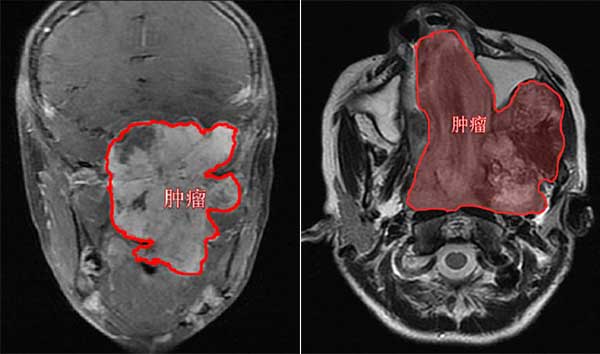

术后影像(MR轴位)

经过全科讨论和反复推敲,由鼻专科邱前辉医师和头颈专科陈良嗣医师组成的手术团队,采用“改良Weber-Fergusson切口和颌下切口联合入路”,通过内镜辅助,历经3个小时,顺利完整切除重达半斤的肿瘤。术后小朱康复良好,容貌也复原了。